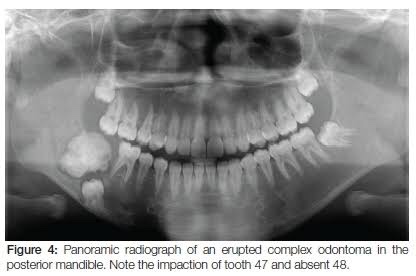

1. Complex Odontoma:

• Location: Posterior region of either Jaw. (70% – Mandibular Molars)

• Composed of haphazardly arranged dental hard and soft tissue with no resemblance to normal tooth.

• Arises from normal tooth follicle.

• Radiographically, Sunburst opacities with thin uniform radiolucent rim.